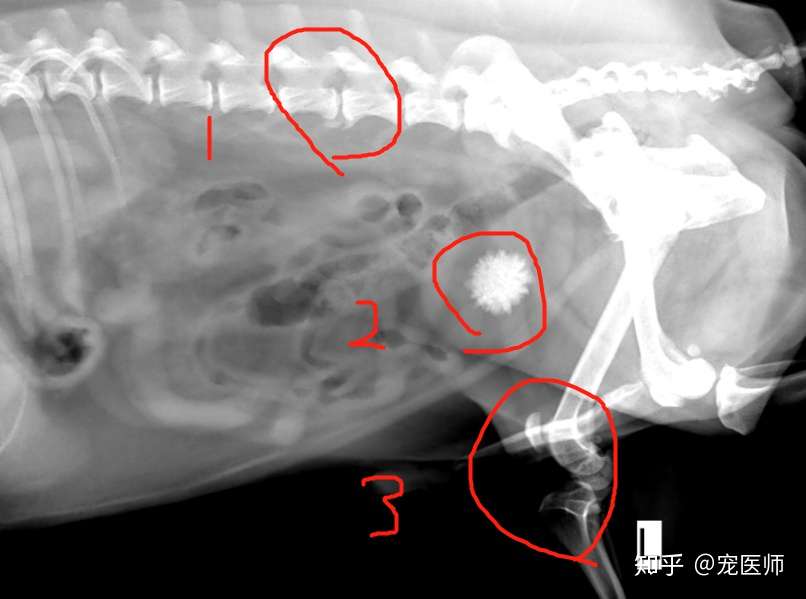

神犬乔巴 狗狗膀胱结石怎么办 知乎

犬 膀胱結石. 犬の尿石症 コーギーの1例 手術で膀胱結石を摘出しました 尿石症とは? 尿石症(尿路結石)とは、尿路である腎臓(腎盂)、尿管、膀胱または尿道のいずれかに結石が形成される病気です。 猫の特発性膀胱炎(FIC) 猫のおしっこに関する病気を総称して猫下部尿路疾患(FLUTD)と呼びます。 その症状として、血尿、頻尿、排尿時に痛がる、ト 排尿障害 〝何度. 膀胱と腎臓を繋ぐ管に出来る尿管結石 3膀胱に出来る膀胱結石 4尿道に石が詰まる尿道結石 犬の結石には4種類あり原因となる野菜・食べ物は異なる. 犬の膀胱・尿道結石の一例 小手指ペットクリニック 16年11月28日 8才のワンちゃんが、昨日から尿が出ずに元気がないとのことで来院されました。 レントゲンを撮ると、膀胱内に7個程度、尿道に3個(ペニス先端から10cmに2個、13cmに1個)の石が.

犬 膀胱結石・尿道結石 チワワ 10歳11ヶ月齢 去勢オス 71kg 頻尿と血尿、排尿障害を主訴に来院 腹部と陰茎の触診検査にて結石症が疑われたため、 レントゲン検査を行い、膀胱結石および尿道結石、腎臓結石と診断した 尿道内にぎっしりとつまった結石は、カテーテルにて膀胱内に押し戻し、膀胱切開にて膀胱結石を摘出した 腎臓結石はに対する外科処置は、腎臓. 犬の膀胱結石 更新日時: ミニチュアダックスフンド、オス (去勢)、11歳 《主訴》血尿、排尿しづらい (少量ずつしか出ない) 《検査》①腹部レントゲン検査 膀胱に結石と思われる不透過性陰影を多数確認 ②腹部超音波検査 膀胱内に結石と思われるシャドーを引く高エコー物を多数確認 ③尿.

与时间赛跑 十字韧带断裂 膀胱结石 髋关节退化 腰椎增生的老年犬 知乎